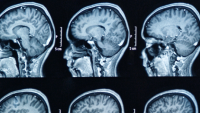

Headache and Pain Disorders

If you suffer from headaches or chronic pain, it can bring your life to a halt. For millions of people, relief seems out of reach. Chronic pain is a common problem worldwide and the most common cause of disability in the United States.

We specialize in providing treatment for the most difficult cases. Our neurosurgeons offer treatment options for patients that have failed to find relief with other therapies. We work with specialists across Columbia to make sure we're making care decisions that lead to the best possible outcomes. We want to help you get back to living your life.

For patients who do not get sufficient pain relief with nonoperative strategies, neurosurgical pain management strategies can offer another option. Our specialists are experienced with performing the latest advanced treatment options to address the most difficult cases.